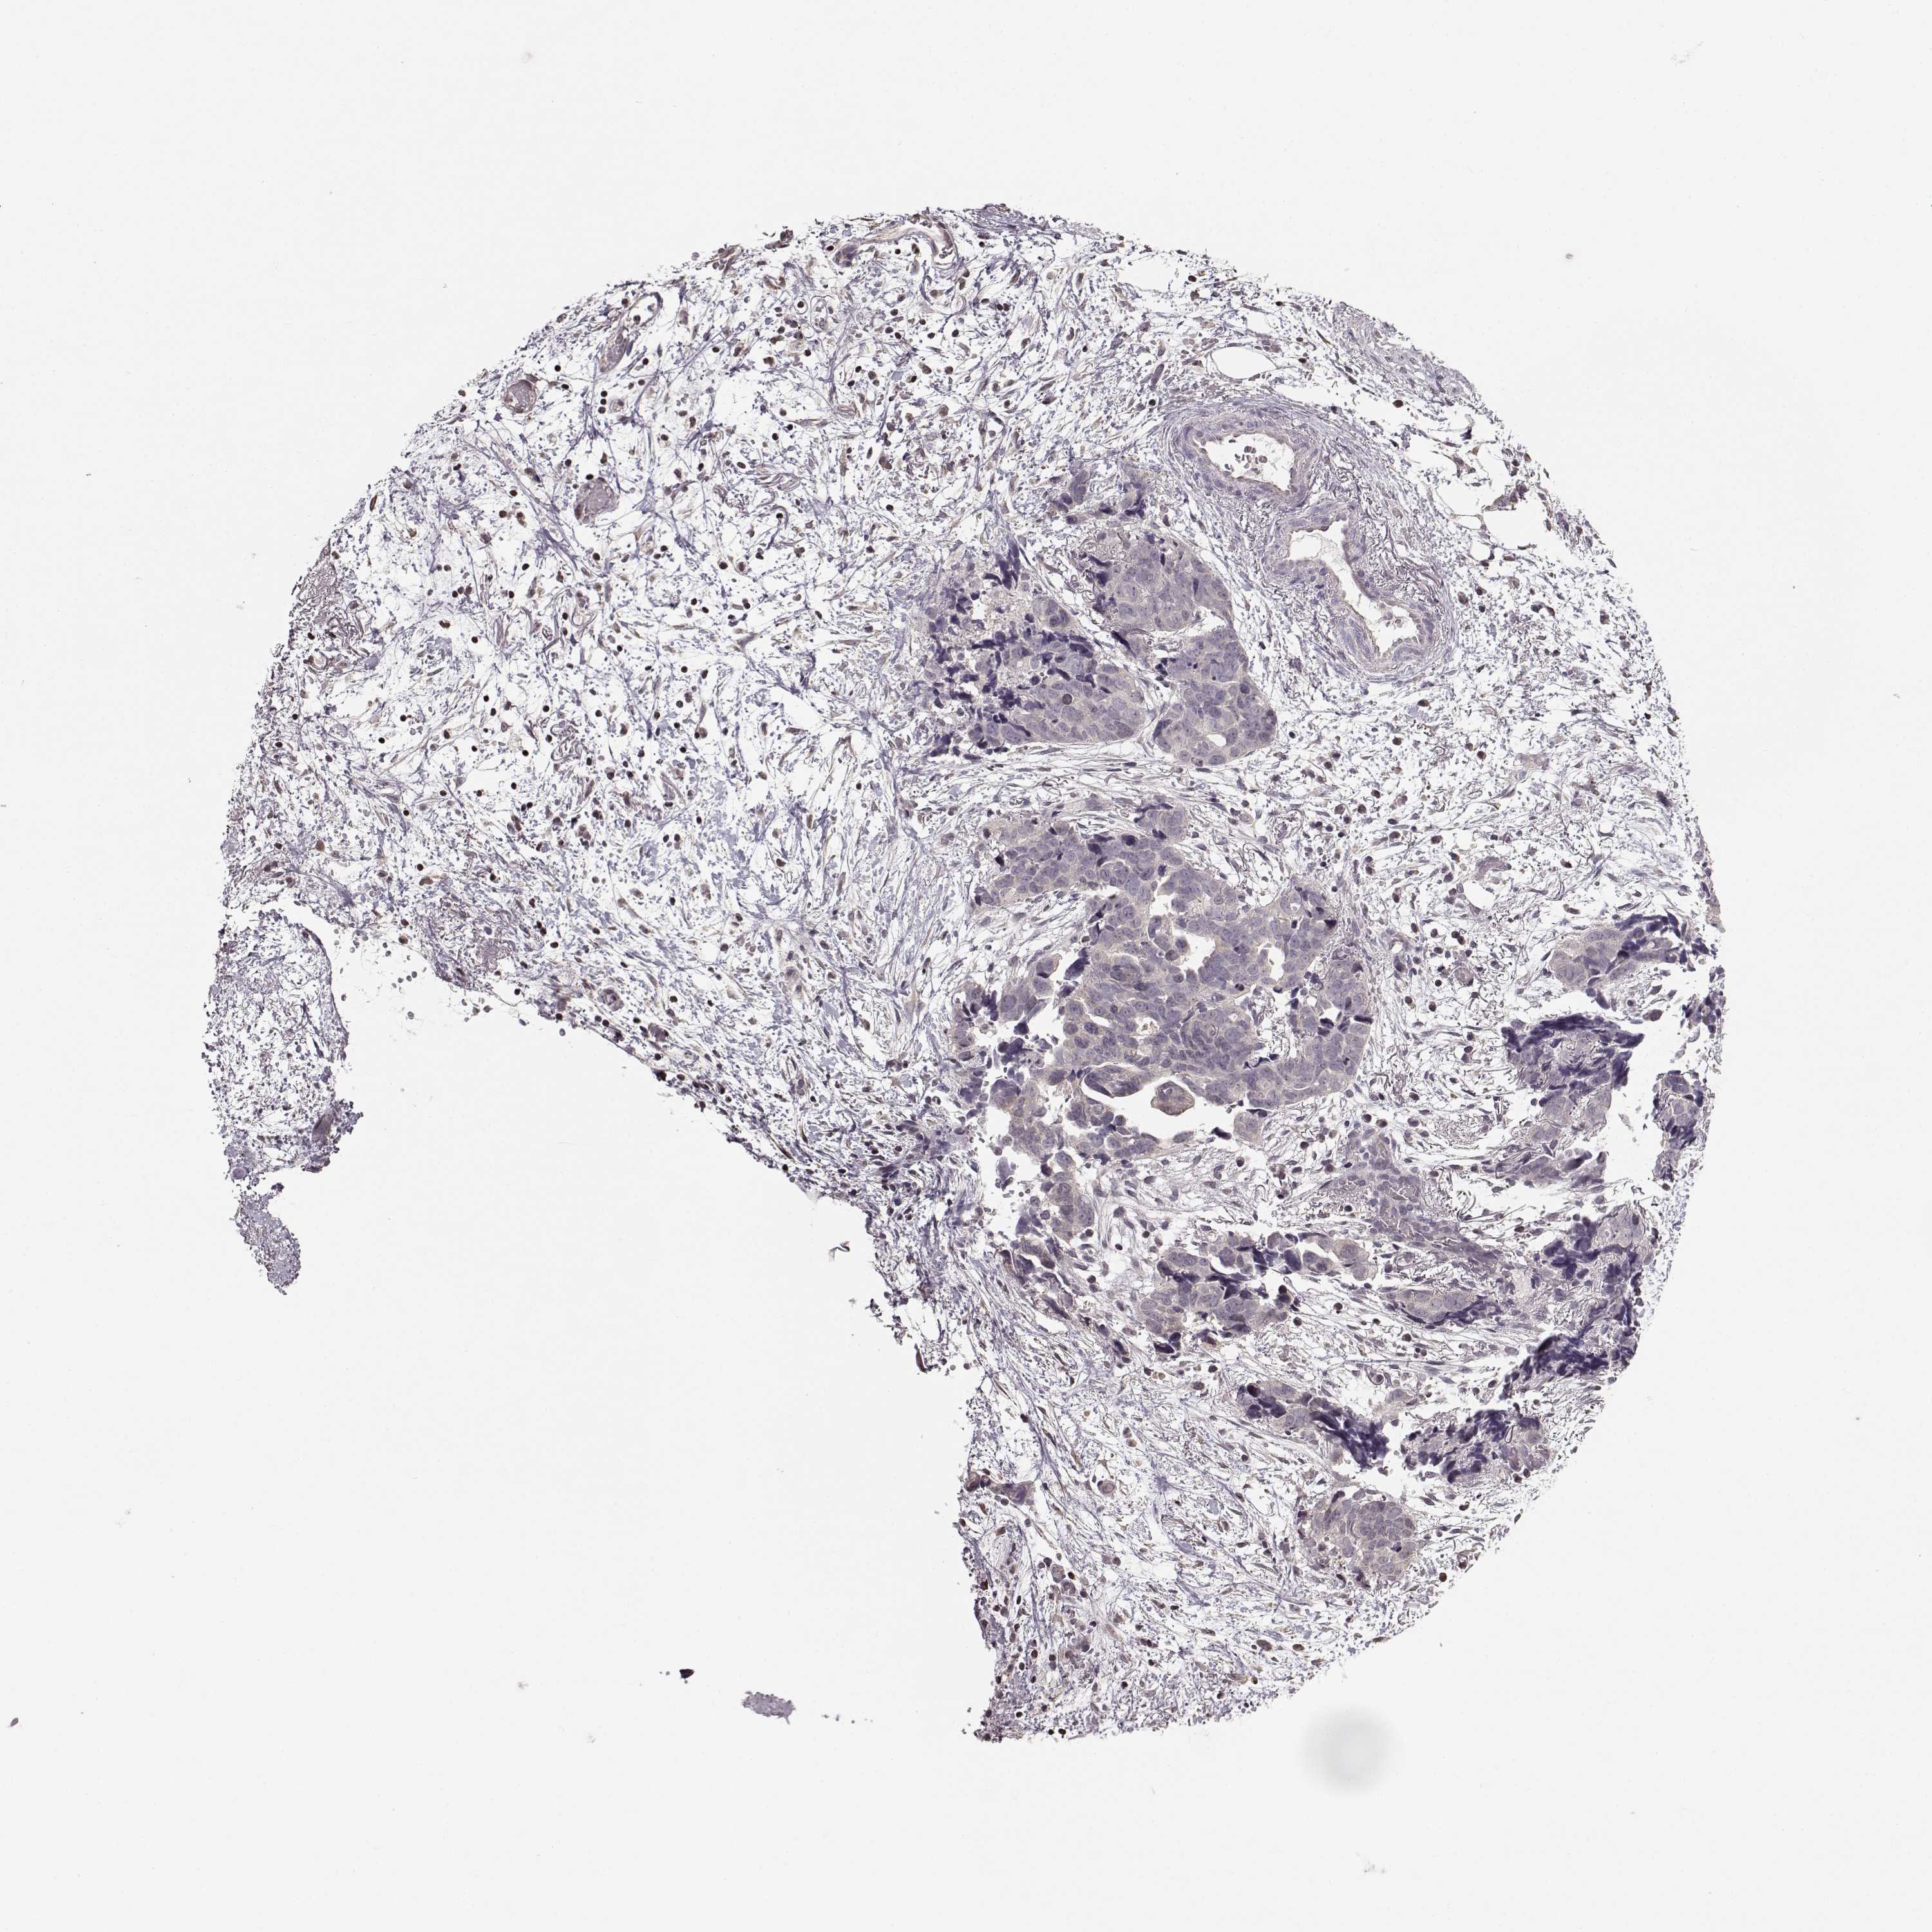

OVARIAN CANCER - Protein expressioni

A mouse-over function shows sample information and annotation data. Click on an image to view it in a full screen mode. Samples can be filtered based on level of antibody staining by selecting one or several of the following categories: high, medium, low and not detected. The assay and annotation is described here.

Note that samples used for immunohistochemistry by the Human Protein Atlas do not correspond to samples in the TCGA dataset.

Antibody stainingi

Antibody staining in the annotated cell types in the current human tissue is reported as not detected, low, medium, or high, based on conventional immunohistochemistry profiling in selected tissues. This score is based on the combination of the staining intensity and fraction of stained cells.

Each image is clickable and will lead to virtual microscopy that enables deeper exploration of all samples and also displays staining intensity scores, fraction scores and subcellular localization as well as patient and tissue information for each sample.

Antibody HPA069703

Antibody CAB023410

Staining

High

Medium

Low

Not detected

Intensity

Strong

Moderate

Weak

Negative

Quantity

>75%

75%-25%

<25%

None

Location

Nuclear

Cytoplasmic/membranous

Cytoplasmic/membranous,nuclear

Cystadenocarcinoma, serous, NOS

Cystadenocarcinoma, mucinous, NOS

Carcinoma, endometroid